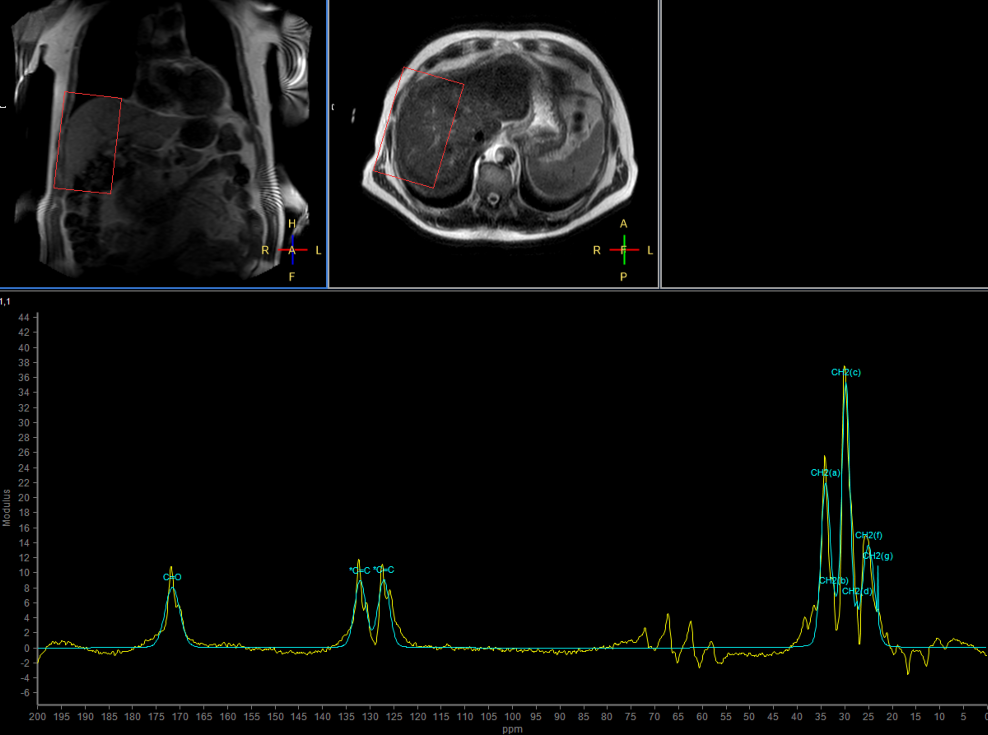

Multi Nuclei - Liver imaging (13C)

Make multi-nuclei imaging and spectroscopy become part of your clinical operations via a seamless integrated workflow for multi-nuclei image acquisition, spectroscopy, reconstruction, and viewing. The nucleus is just a scan parameter like any other sequence parameter. A single ExamCard can be used to run both proton and non-proton imaging. Reconstruction and viewing of non-proton images or spectra, as well as the process for sending the data to PACS is fully integrated, so workflow does not differ from proton imaging. The transmit-receive 13C flex coil, with a 14 cm diameter, is immediately recognized by the ExamCard interface. Improved SNR and simplified spectra* are achieved by combining body coil decoupling with the transmit-receive surface coils.